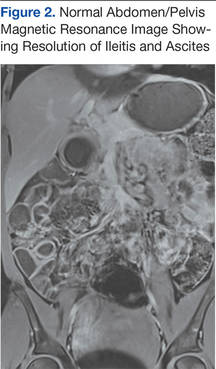

A magnetic resonance enterography was performed shortly thereafter and revealed resolution of the prior bowel wall thickening (Figure 2).